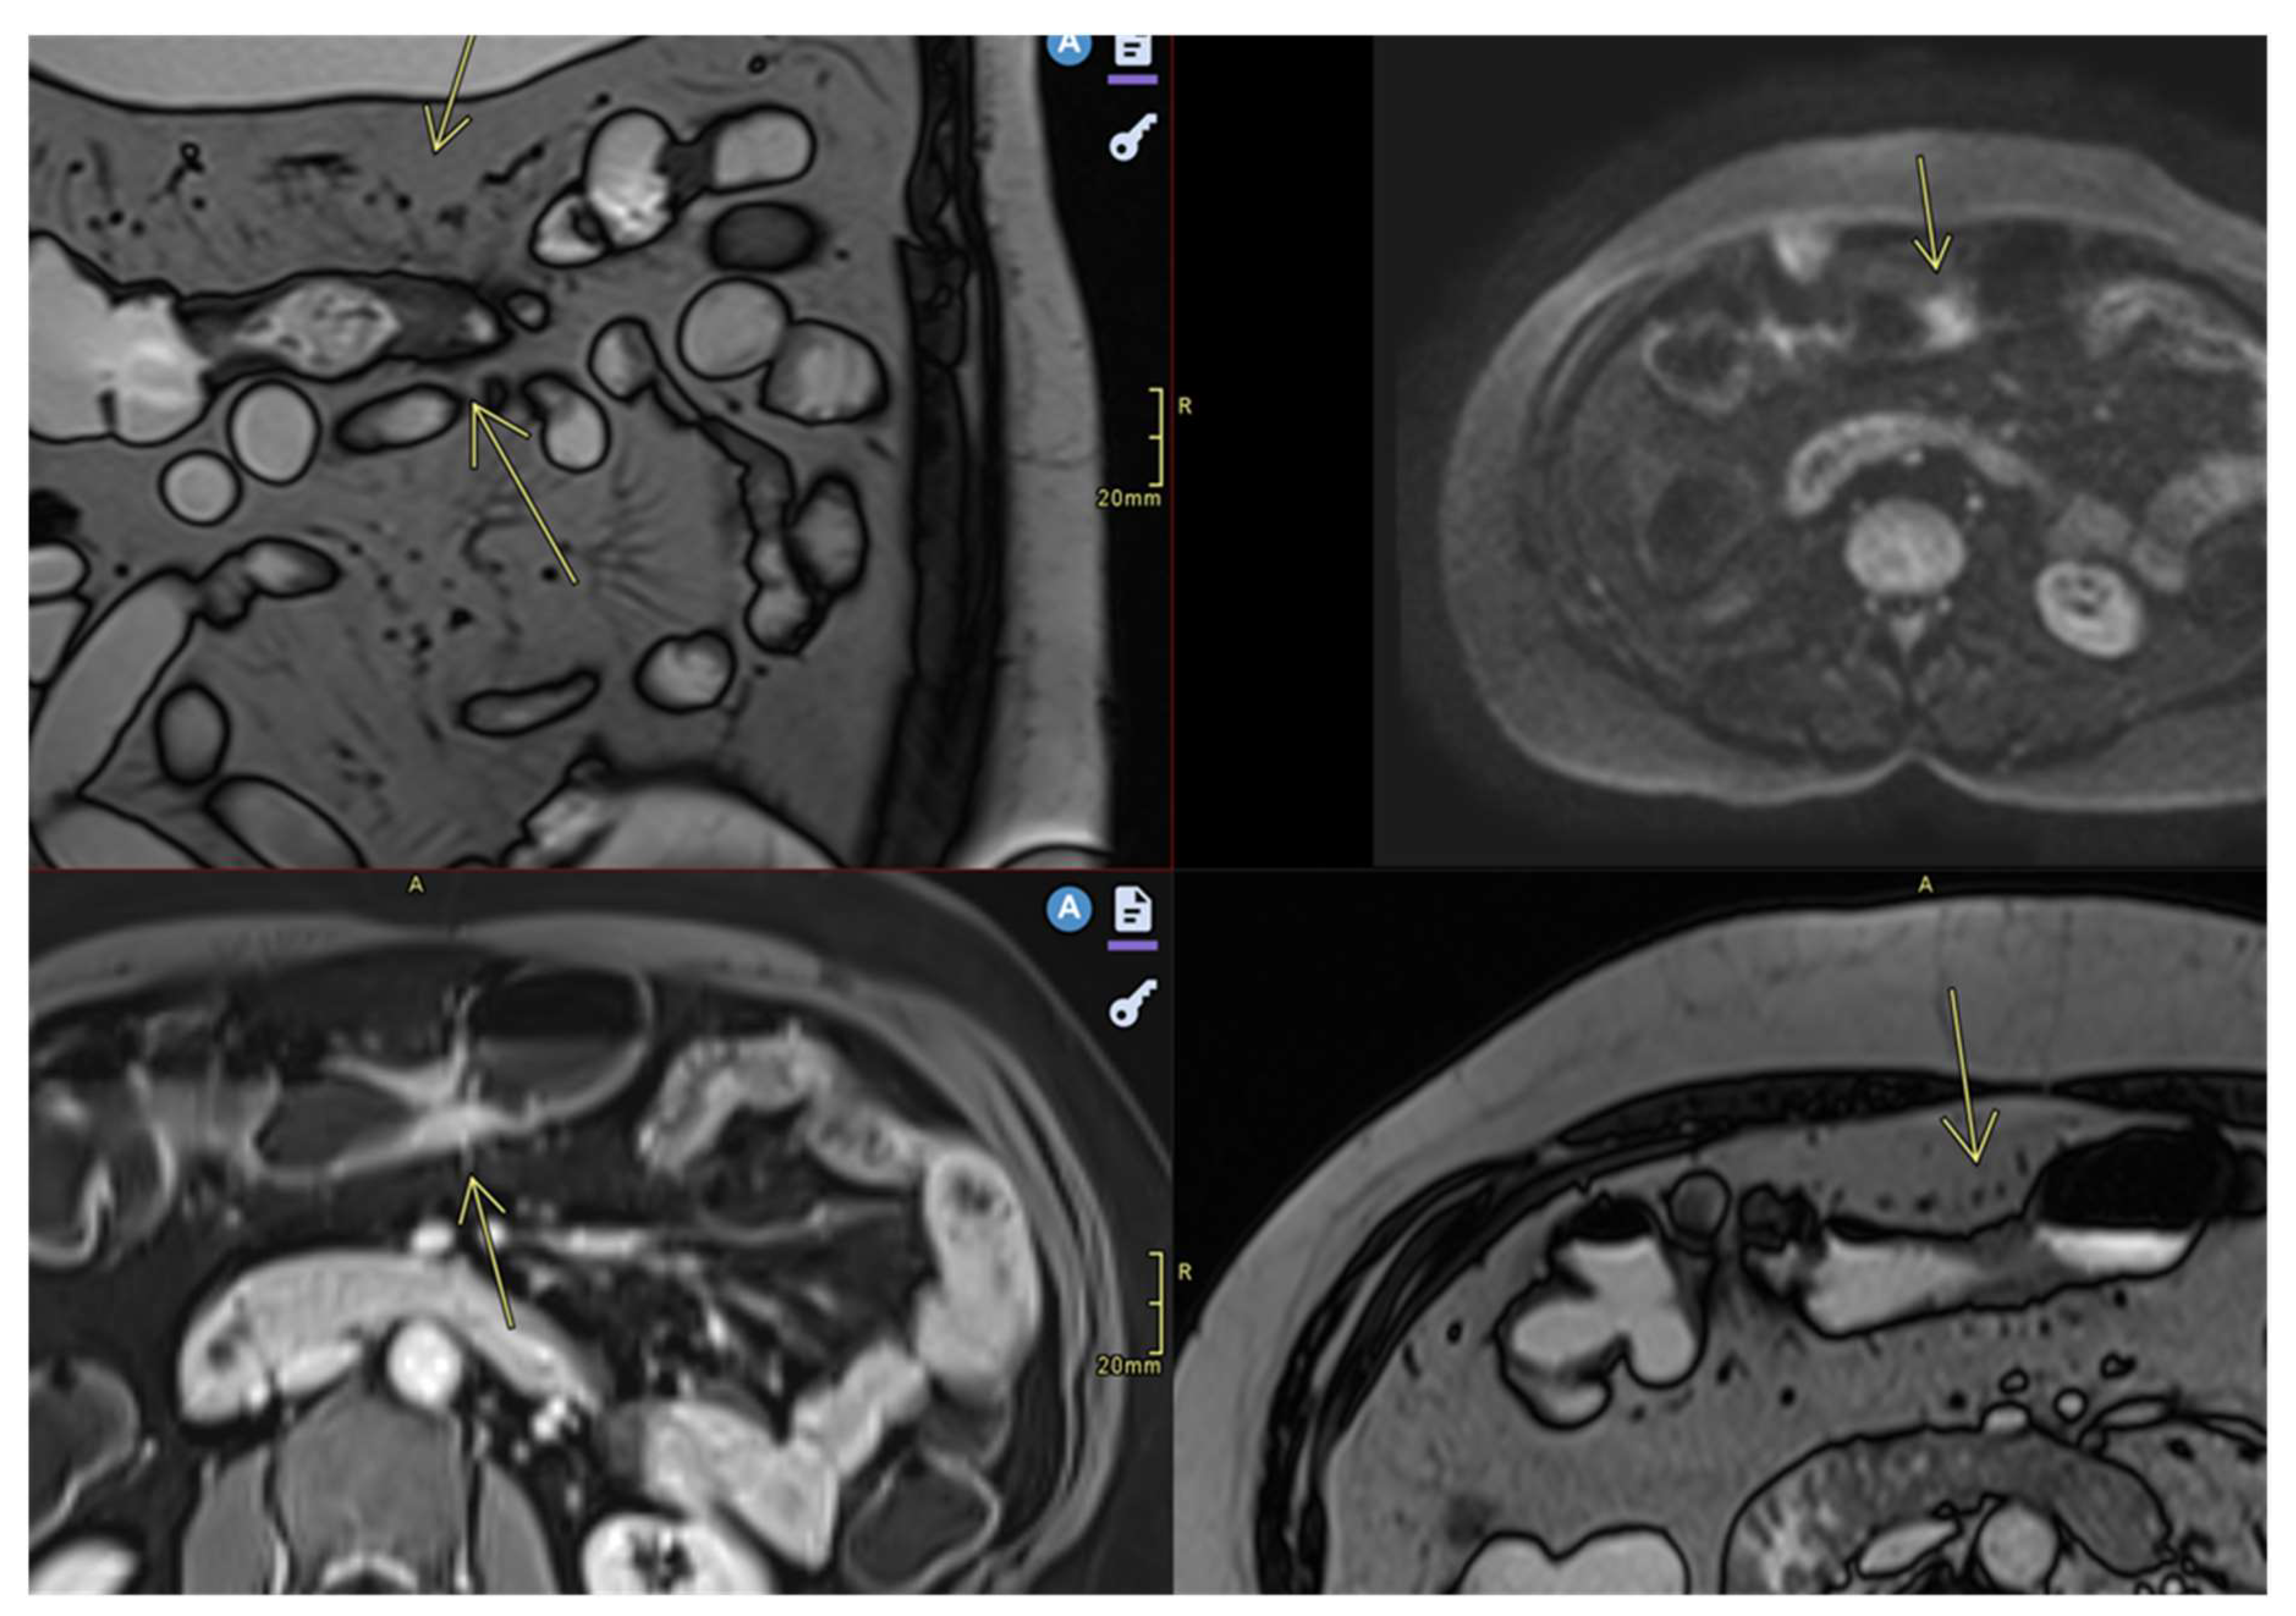

- Ulceration

- Focal defects, fine disruptions of the mucosal contour - small signs of T2 hyposignal or intense post-contrast enhancement[50]

- Requires adequate distension of the small bowel (Figure 4 ).